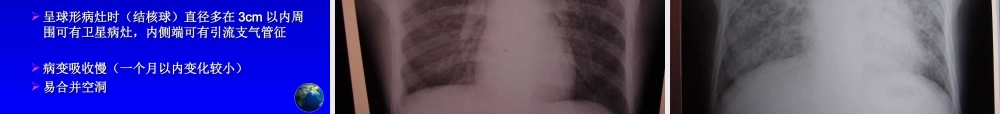

肺结核病的诊断肺结核病的诊断和治疗进展和治疗进展前言前言 肺结核是一种肺部感染性疾病。由肺结核是一种肺部感染性疾病。由于大多数患者是在院外获得,因而于大多数患者是在院外获得,因而属于社区获得性感染肺炎(属于社区获得性感染肺炎( CAPCAP ))一种,它是呼吸科门诊常见的疾病。一种,它是呼吸科门诊常见的疾病。不同国家总延误的中位值不同国家总延误的中位值53.155.452.1718398.584.290.3020406080100120J apanNetherlandsKoreaSolomon IsPhilippinesBangladeshNepalYemenDays前言前言 中国中国 ---- 全球 个结核高负担国家之全球 个结核高负担国家之一一 每年新发病占全球总数 每年新发病占全球总数 %% 每年发生活动性肺结核病人 万每年发生活动性肺结核病人 万例例 其中涂阳肺结核 万例其中涂阳肺结核 万例前言前言 ““ 三个不改变”三个不改变” 结核病患病率和死亡率在传染病中最高不结核病患病率和死亡率在传染病中最高不改变改变 结核病的“六高”不改变结核病的“六高”不改变(感染率、患病率、死亡率、新涂阳率、(感染率、患病率、死亡率、新涂阳率、耐药率、农村患病率)耐药率、农村患病率) 结核病患病人数在全球不改变结核病患病人数在全球不改变吴仪副总理吴仪副总理 20062006 年全国结核病防治工作电视电话会议年全国结核病防治工作电视电话会议结核病感染率结核病感染率 全 国全 国 : 44.5%: 44.5% 广 东 省广 东 省 : 44.5%: 44.5% 广 州 市广 州 市 : 67.4%: 67.4% 农 村农 村 : : 35.9%35.9% 城 镇城 镇 :: 59.4% 59.4% 城 市城 市 :: 55.1% 55.1% 大 学 生大 学 生 :: 38.9% 38.9%中国防痨杂志中国防痨杂志 .2002.2002 ,, 2424 (( 22 ))全国结核病死亡率( 全国结核病死亡率( / / 万)万) 全 国 全 国 :: —— 结核病 结核病 9.89.8 — — 肺结核 肺结核 8.88.8 广东省 广东省 : 4.5: 4.5 广州市 广州市 : 5.5: 5.5 死亡原因死亡原因 排 位: 排 位: 99 全 身 衰 竭全 身 衰 竭 心肺功能不全 心肺功能不全 81%81% 咯 血咯 血中国防痨杂志中国防痨杂志 .2002.2002 ,, 2424 (( 22 ))050100150200250300350400全国广东省广州市活动性涂 阳菌 阳2000 年活动性肺结核患病率患病率(1/10万)中国防痨杂志中国防痨...